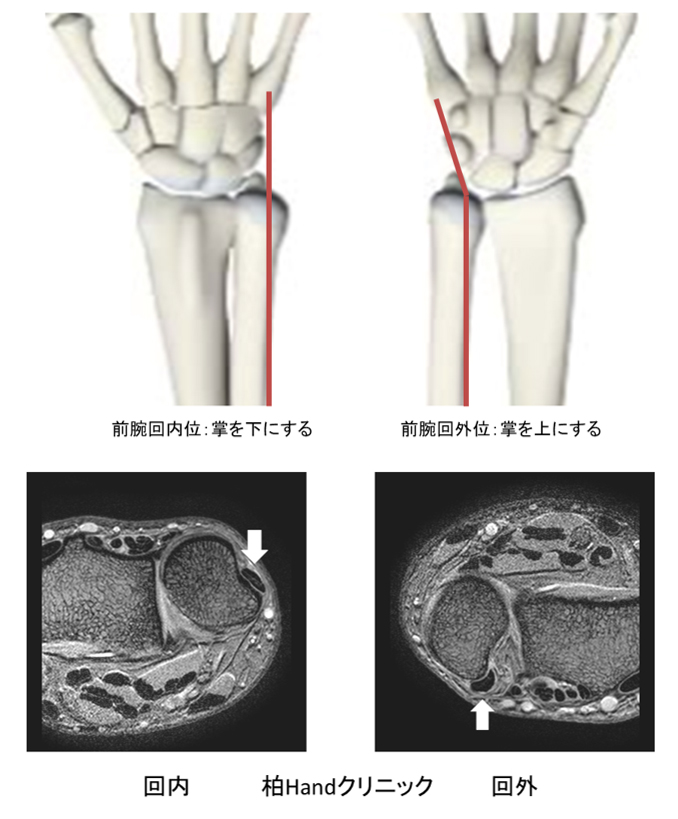

尺側手根伸筋腱炎、周囲炎手の治療専門サイト。

手をつくと「手首」が痛い 小指側の腱鞘炎 原因と対策は:手のお話:日経Gooday グッデイ。